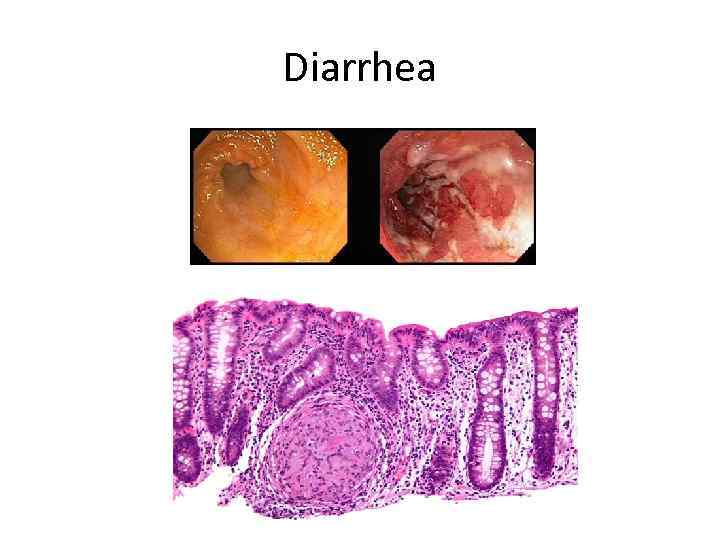

Diarrhea